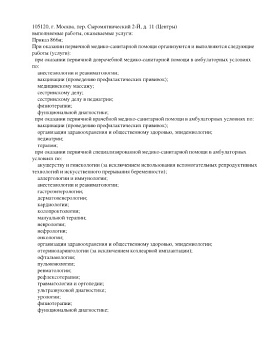

Лицензии